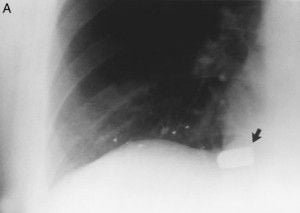

Este sujeto huyendo de arresto, recibió un disparo en la espalda por un agente de policía.

(A) Vista frontal muestra partículas de plomo que van desde el

herida de entrada, que es en la porción media del hemitórax derecho justo por encima del hemidiafragma derecho, con pequeñas partículas de plomo que conducen hasta el lugar de descanso final de la bala detrás de la sombra del corazón (flecha).

(B) La vista lateral muestra que la bala es realmente muy superficial

debajo de la piel de la parte posterior. La bala golpeó la costilla, a continuación, seguido de su curvatura para venir a descansar a una distancia considerable de la herida de entrada.